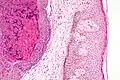

Histologically, molluscum contagiosum is characterized by molluscum bodies (also known as Henderson-Patterson bodies) in the epidermis, above the stratum basale, which consist of cells with abundant large granular eosinophilic cytoplasmic inclusion bodies (accumulated virions) and a small nucleus that has been pushed to the periphery.[19][20]

Low magnification micrograph of a molluscum contagiosum lesion

Low-magnification micrograph of molluscum contagiosum, H&E stain

High-magnification micrograph of molluscum contagiosum, showing the characteristic molluscum bodies, H&E stain